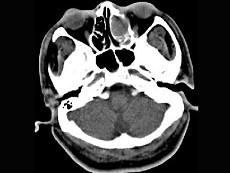

男,34岁,头痛、头晕3个月余,CT检查如图,最可能诊断为 ( )

• A.筛窦炎

• B.筛窦黏液囊肿

• C.筛窦息肉

• D.筛窦乳头状瘤

• E.筛窦癌

答案: B